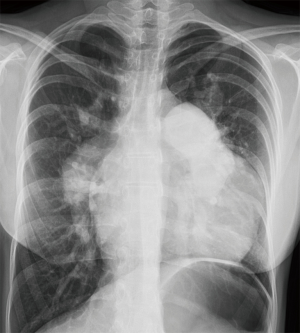

Tetralogy of Fallot (TOF) is the most common cyanotic congenital heart disease (CHD); its prevalence is estimated at around 5/10,000 births (1). Furthermore, due to the success of pediatric cardiac surgery and pediatric cardiology, the population of adults with TOF is growing steadily, with over 90% of children with CHD now surviving into adulthood (2). This relatively new population of adult patients, which now outnumbers the pediatric TOF population, poses further challenges for clinicians. Cardiac imaging has rapidly evolved, from relying exclusively on cardiac catheterization and chest radiography (Figure 1) to today’s more advanced imaging techniques: echocardiography, cardiac magnetic resonance (CMR), and cardiovascular computer tomography (CT) (3). Because of the complex nature and diversity of these population, as well as the limitations of each modality, it is increasingly recognized that an expert multidisciplinary team with a multimodality imaging approach is necessary for their clinical management (4).